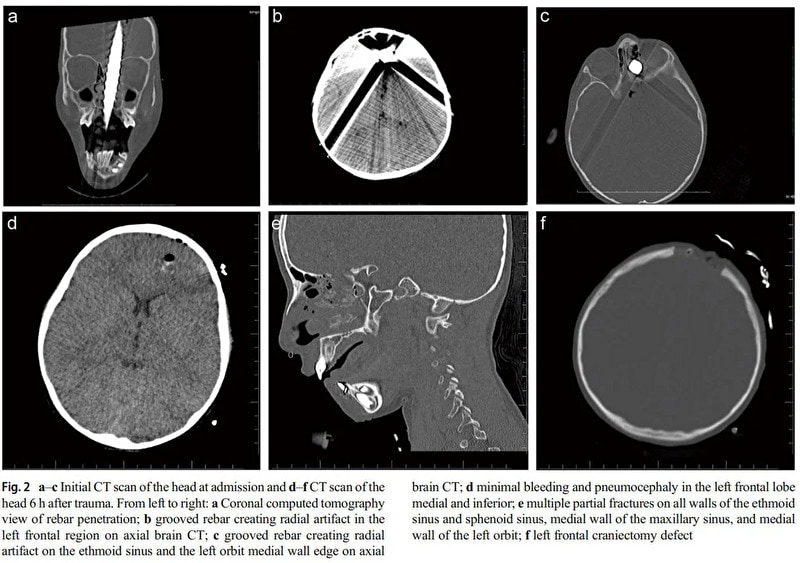

gif_animation トルコにて、「不死身の人間の画像」として国中を騒がせている衝撃的な4枚。高さ5mから落下し、鉄筋が頭を貫通するも死ななかった(手術後回復した)9歳の男の子の姿がこちら。ヤバすぎる。

※ 画像